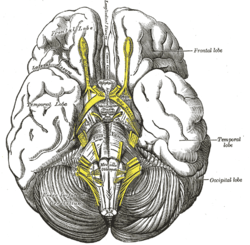

Lobes Base of brain.

Base of brain. Human brain showing the four major lobes of the cerebrum. Beneath the cerebral cortex are the cerebellum, pons, olive, and medulla oblongata

Human brain showing the four major lobes of the cerebrum. Beneath the cerebral cortex are the cerebellum, pons, olive, and medulla oblongata Drawing to illustrate the relations of the brain to the skull.